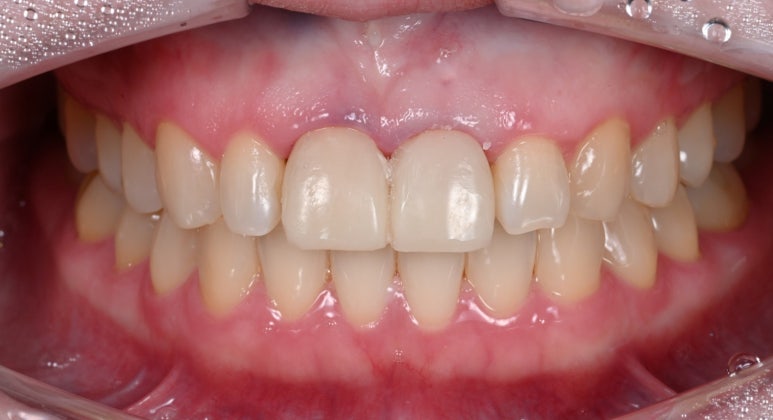

25.08.11 임시치아 장착

25.09.04 임시치아 장착 약 3주 후

25.09.11 치료 후